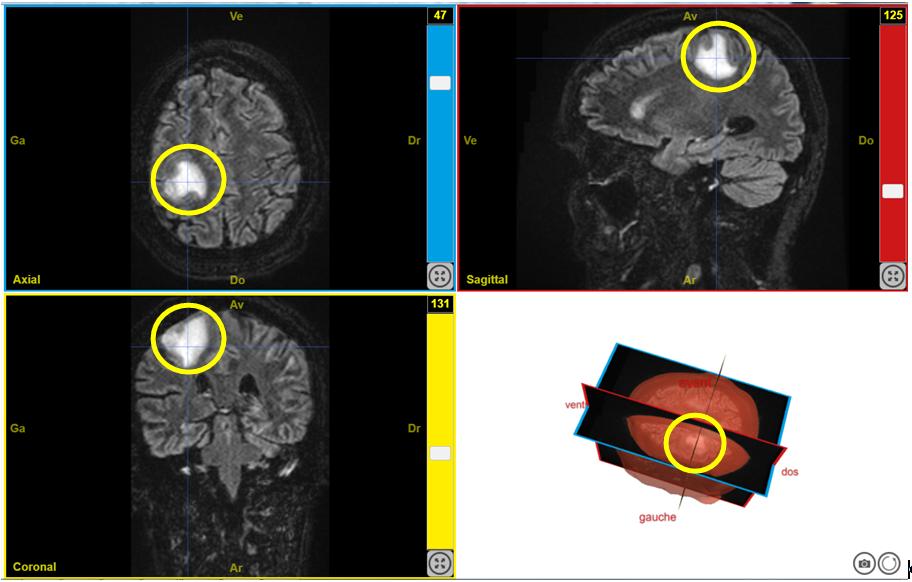

Capture Deficit moteur T2FLAIR